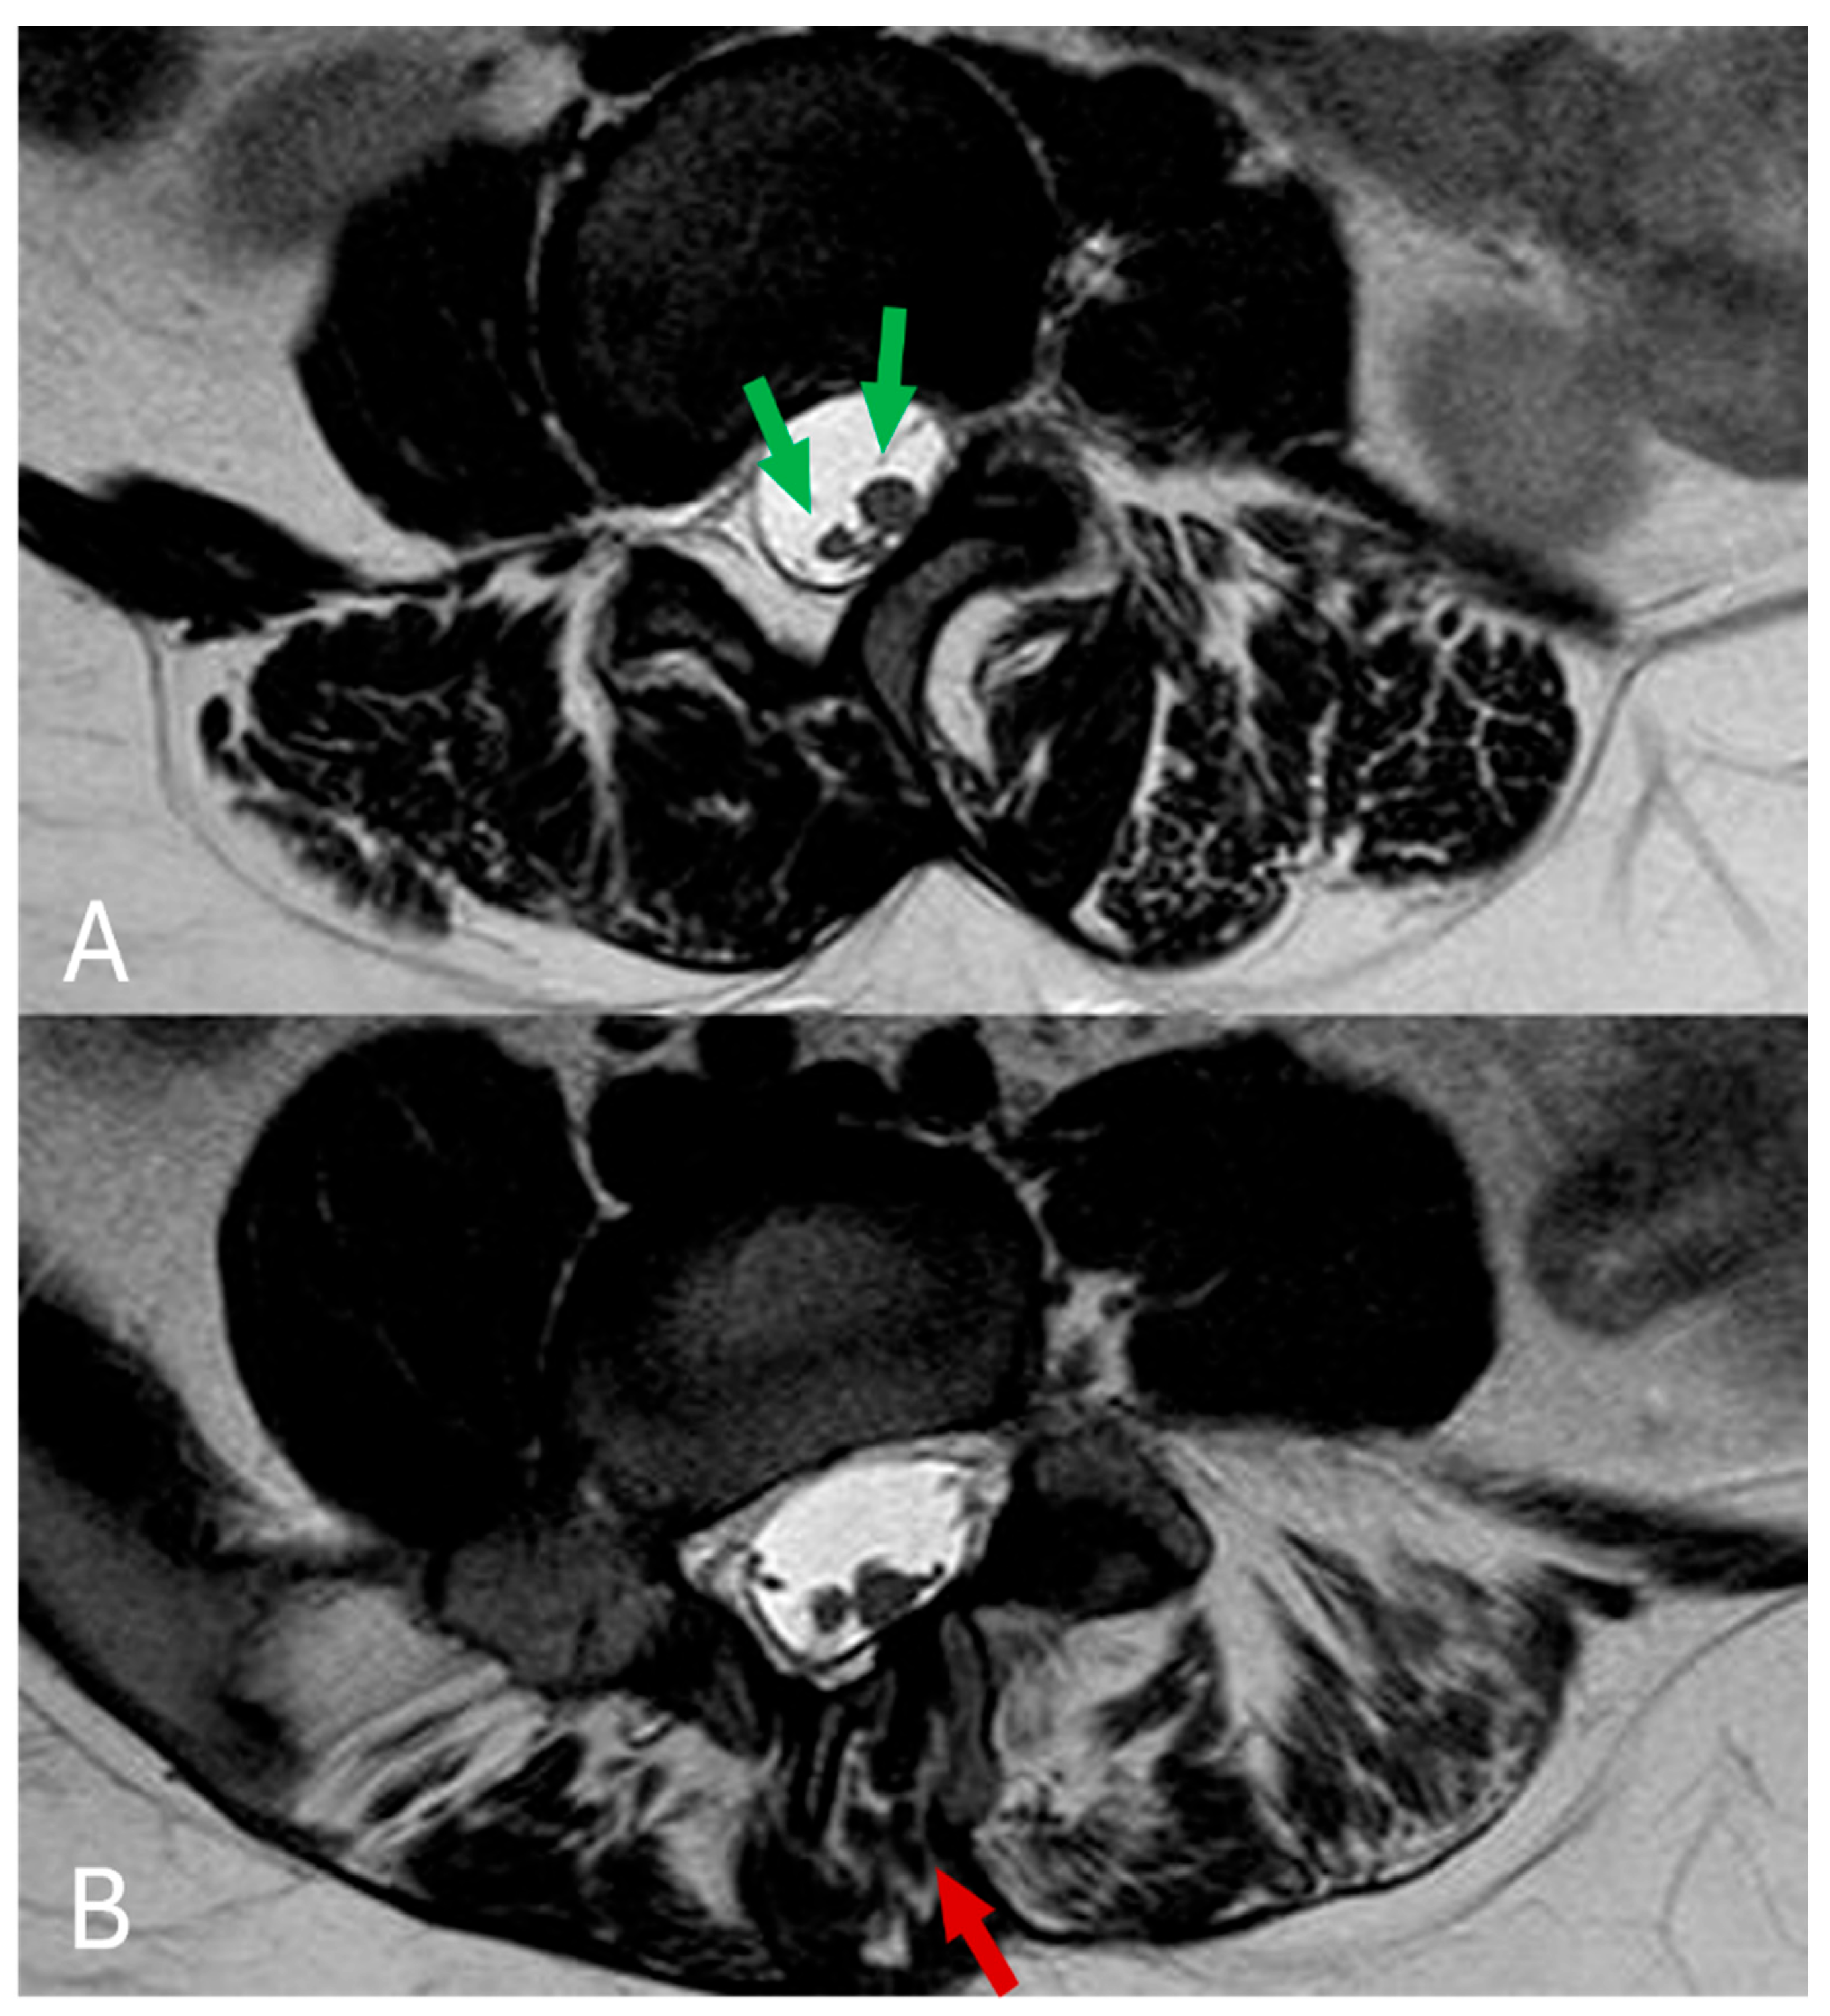

Figure 4.

(A,B) In the axial plane, T2 TSE imaging reveals diastematomyelia across multiple levels (green arrows), along with evident defects in the vertebral posterior arch (red arrows).